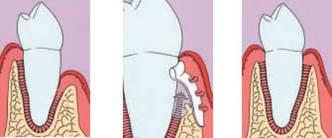

Jedná se o vyzvednutí membrány, která čelistní dutinu vystýlá, pod vyzvednutou membránou vznikne kapsa, kam se umístí augmentační materiál, do kterého se zavedou implantáty.

Souprava pro laterální přístup k sinus liftu, speciálně navržena pro bezpečný a méně invazivní laterální přístup k nadzdvihnutí membrány sinu. LAS Kit nabízí v závislosti na anatomii dutiny ústní a plánech operace různé využití.

CAS Kit

Souprava pro krestální přístup k operaci sinus liftu tím, že se vytvoří v kosti kónický odštěpek, kterým lze membránu bezpečně nadzvednout.